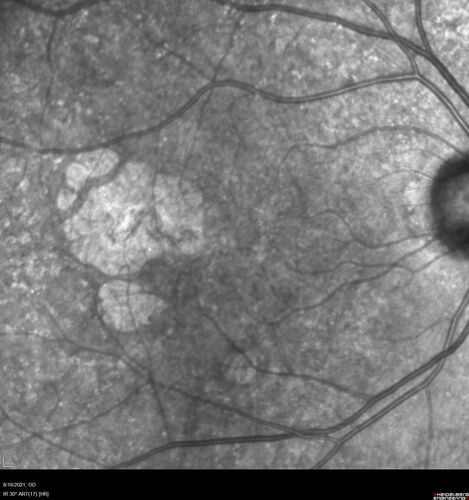

Geographic Atrophy with recent vision loss left eye

80 year old Recent vision loss in the left eye for about 6 weeks.

Hyperlipidemia, HTN, Angina, history of TIA’s

ASA daily

VA 20/25 OD, 20/63 OS (was 20/40 5/3/21 at patients first visit)

AC pseudophakic